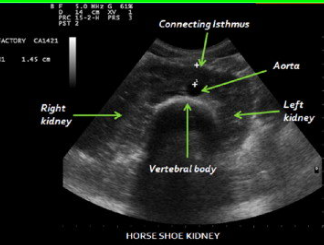

Horseshoe Kidney

Most common fusion anomaly. Lower poles of the kidneys are joined across the midline by a band of soft tissue. +Men. Generally unimpaired – but if obstruction present, surgery possible

horseshoe kidney image